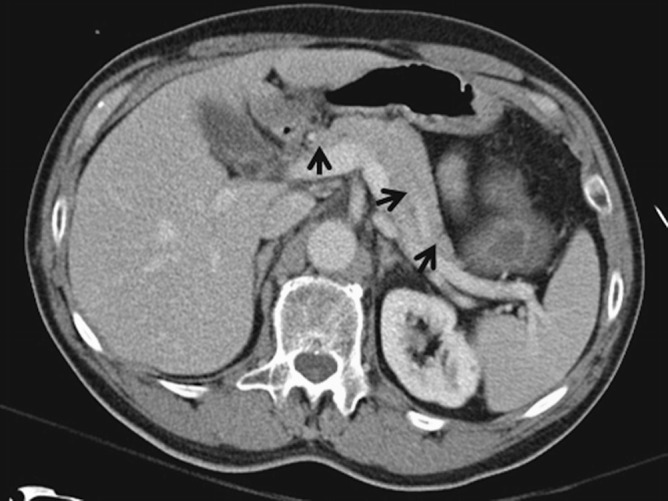

If the patient is not clinically improving after several days of conservative management, CT scan is helpful as it may explain the lack of improvement (such as whether there is pancreatic necrosis). Beyond the first week, CT scan is helpful in the situation where a patient develops worsening abdominal pain, fever, and sepsis, as it may demonstrate a pseudocyst or a pancreatic abscess (these local complications do not manifest on admission) (◘ Figs. 20.3, 20.4, and 20.5).

Fig. 20.3.

Axial CT with a normal-appearing pancreas. (Black arrows: normal pancreas)